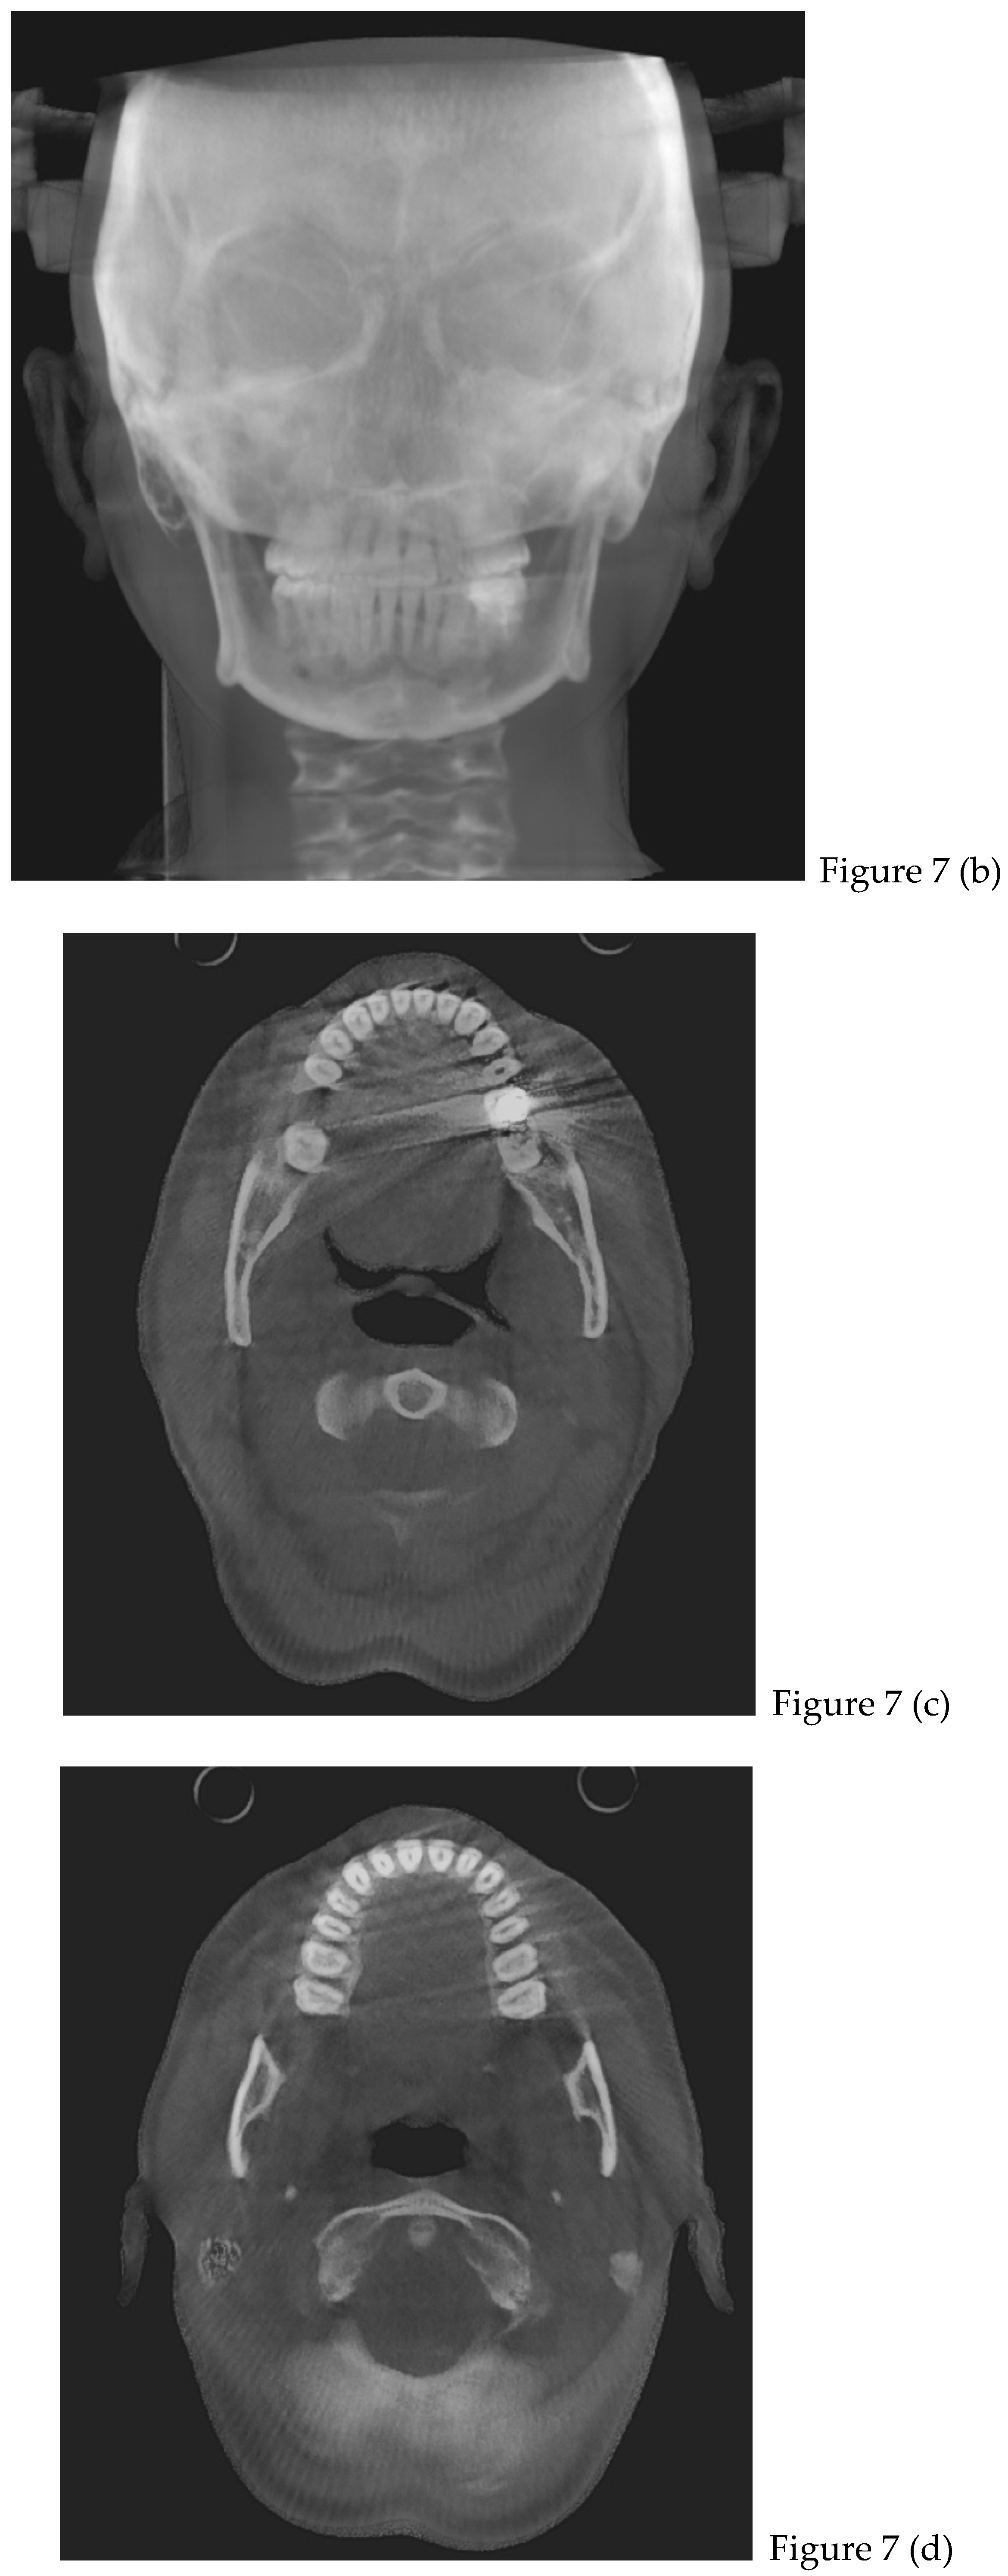

2.2. Cone Beam CT Analysis

| CBCT (t0) | |

| after 8 months | Retainers + CBCT (t1) + final photos |